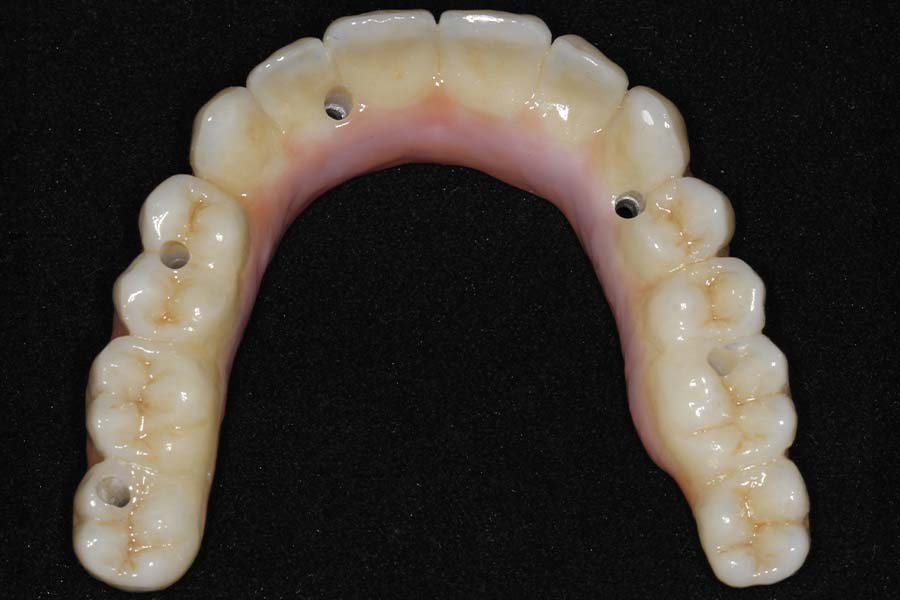

Tissue-view of the final implant bridge. Note the convex (cleansable) contours. This is a wide departure from “All-on-4” treatment which is virtually uncleansable.